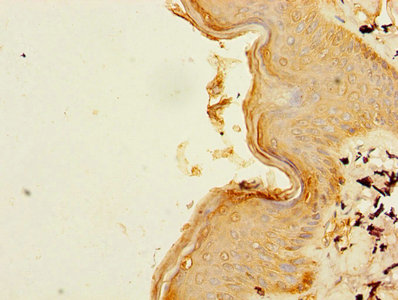

DescriptionB3GNT2 Polyclonal Antibody. Unconjugated. Raised in: Rabbit.

ImmunogenRecombinant Human N-acetyllactosaminide beta-1,3-N-acetylglucosaminyltransferase 2 protein (29-397AA)

ApplicationELISA, WB, IHC; Recommended dilution: WB:1:500-1:2000, IHC:1:20-1:200